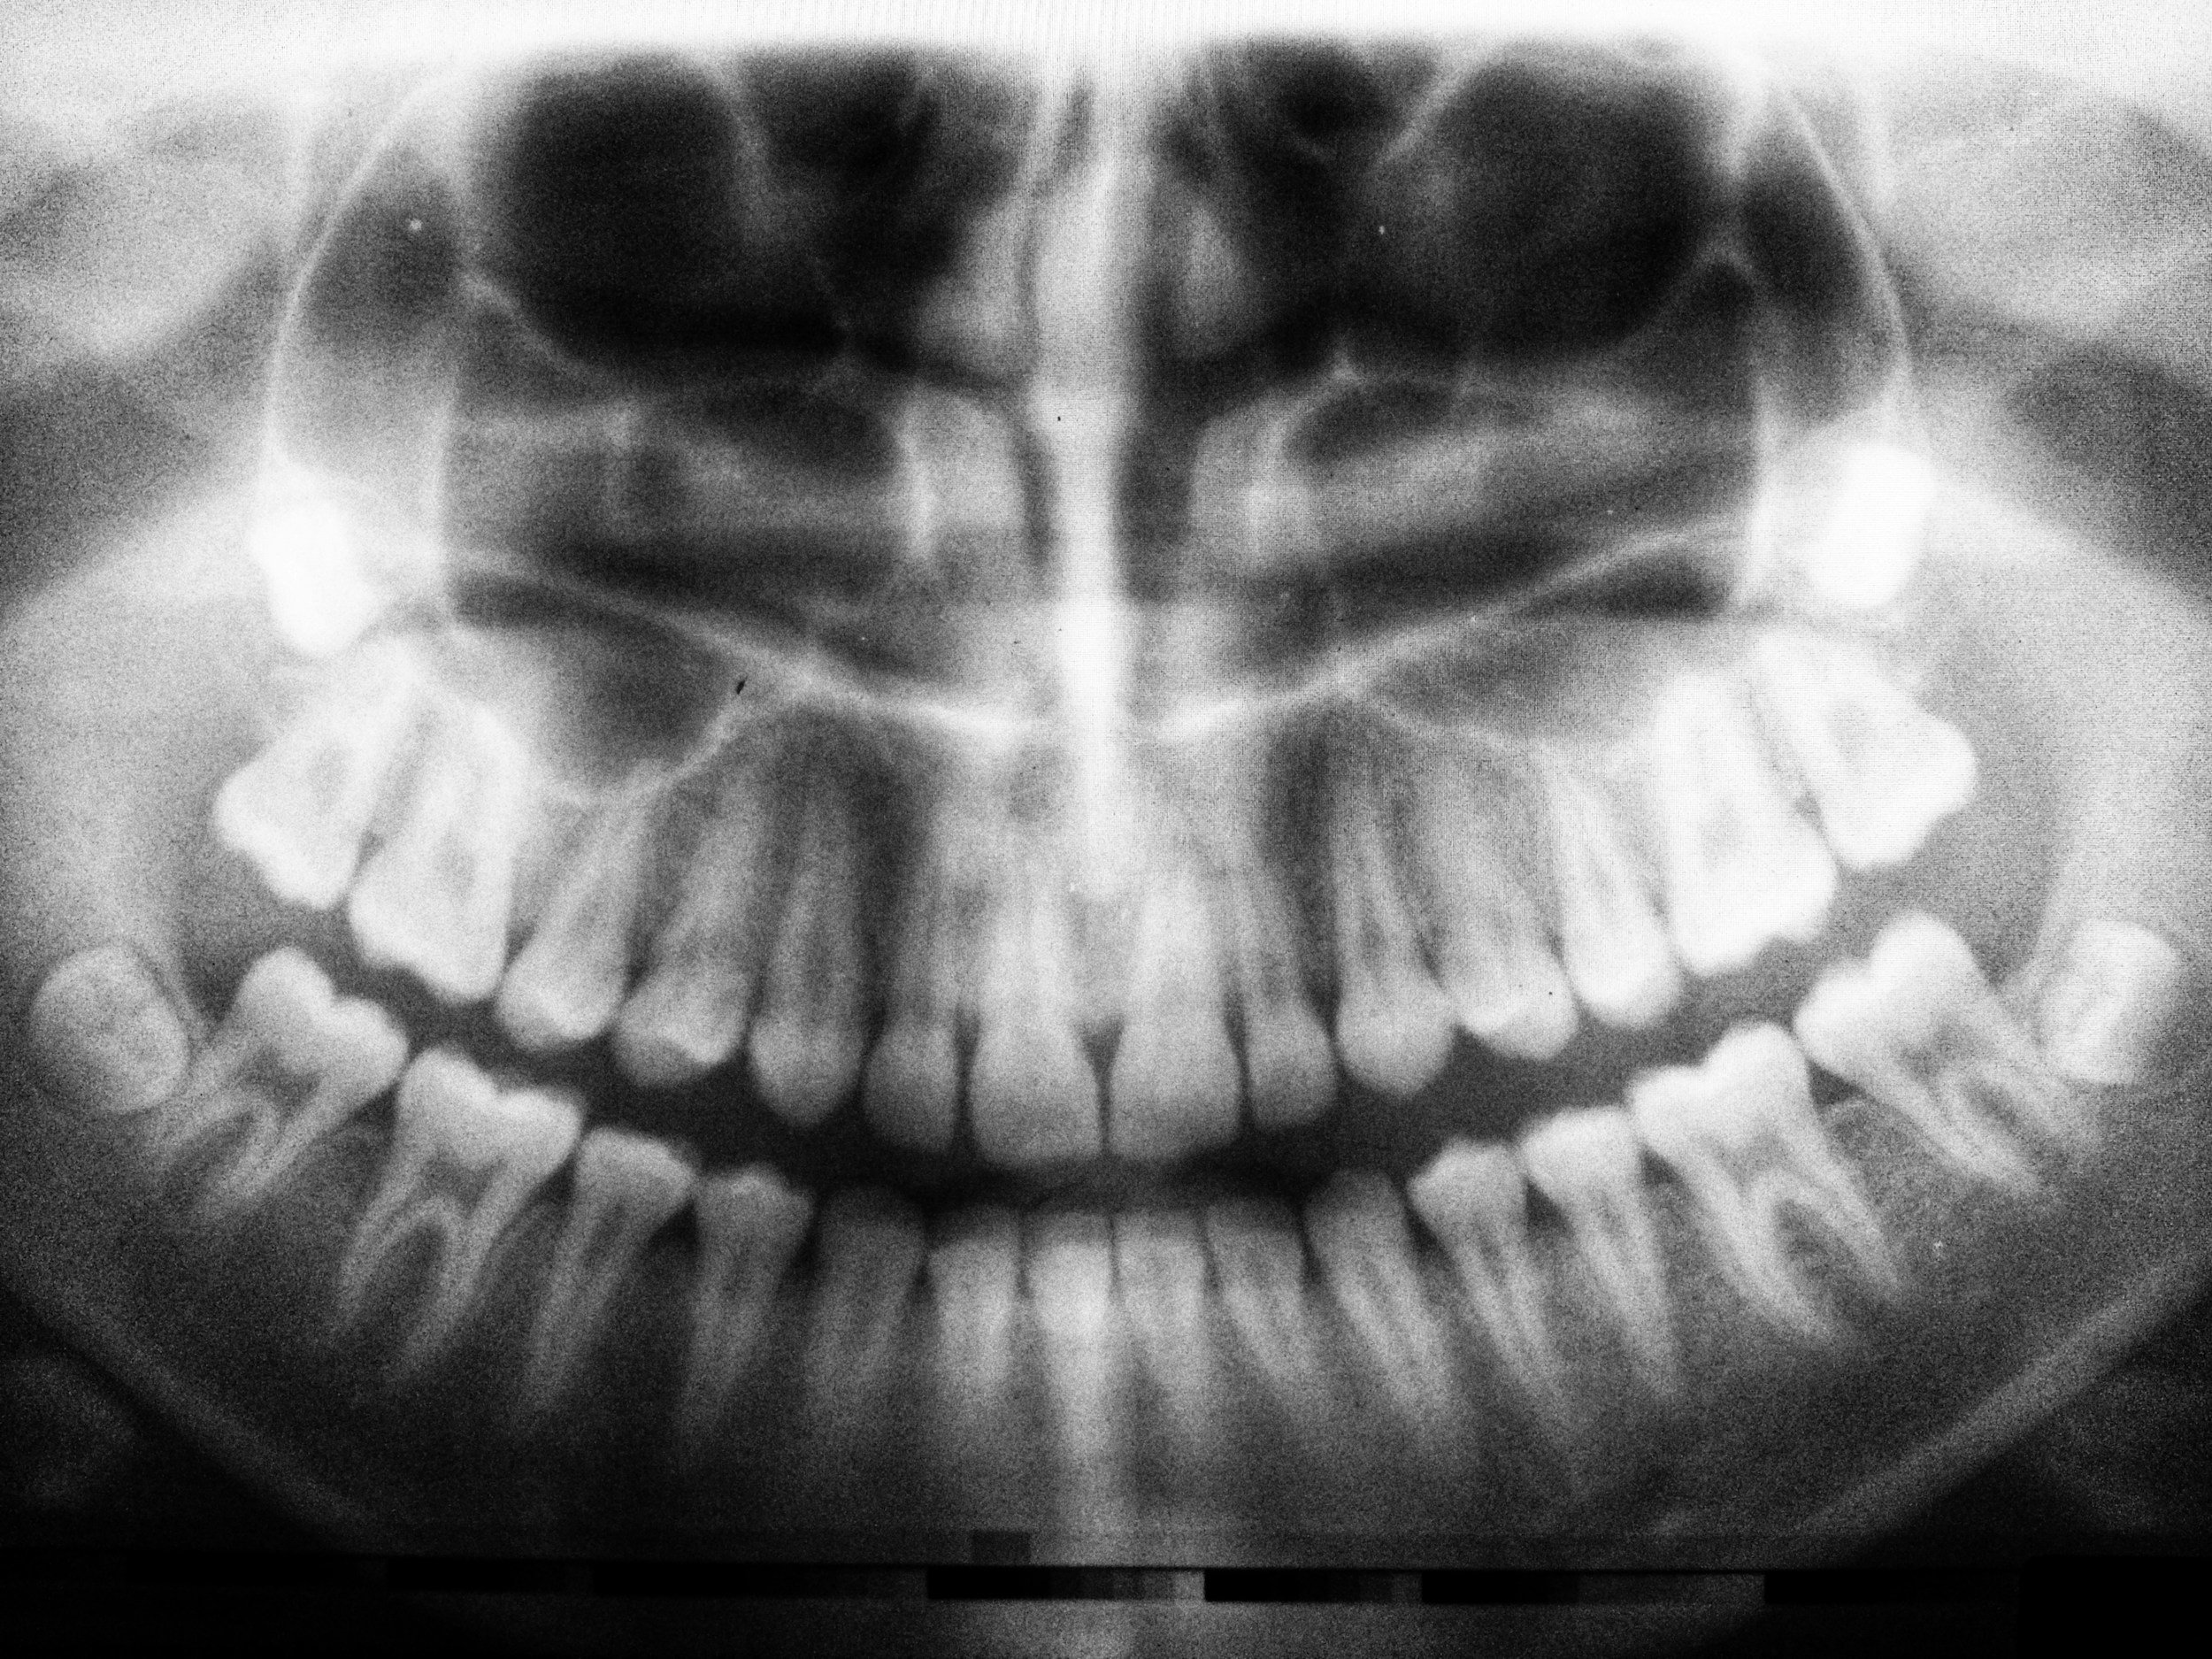

A thorough examination and X-rays by your dentist or oral surgeon can determine whether removal is necessary.

1. Consultation and Evaluation: An initial exam and X-rays to assess the position of your wisdom teeth.